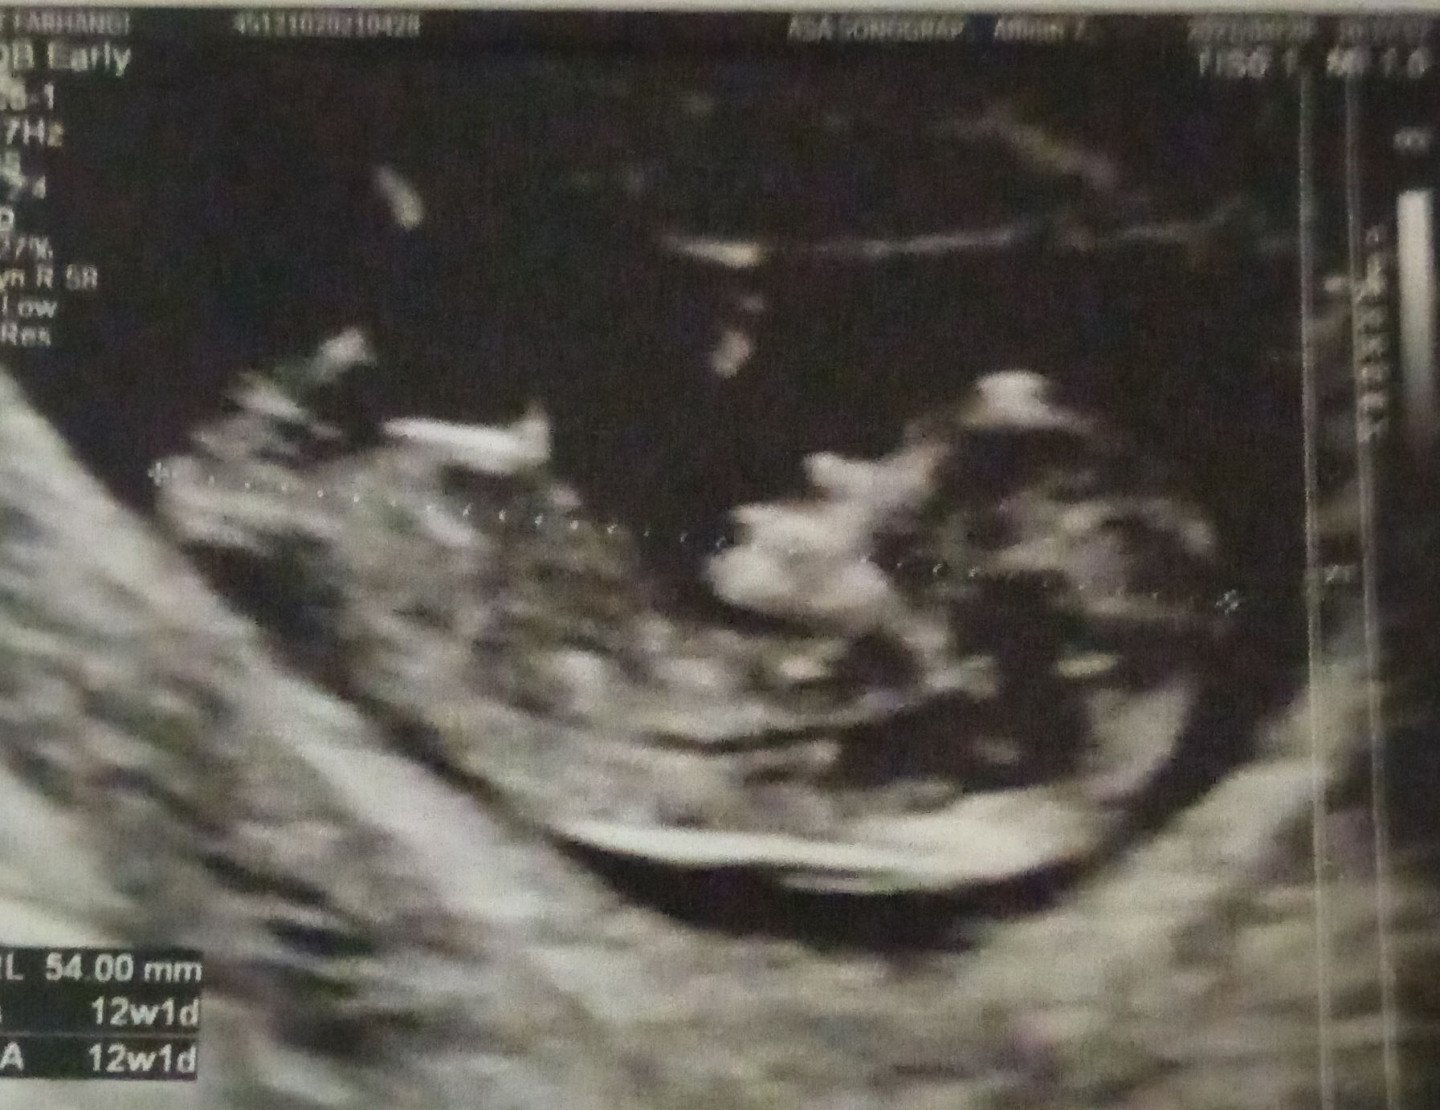

۱۲ هفته و ۱ روز♥️♥️♥️